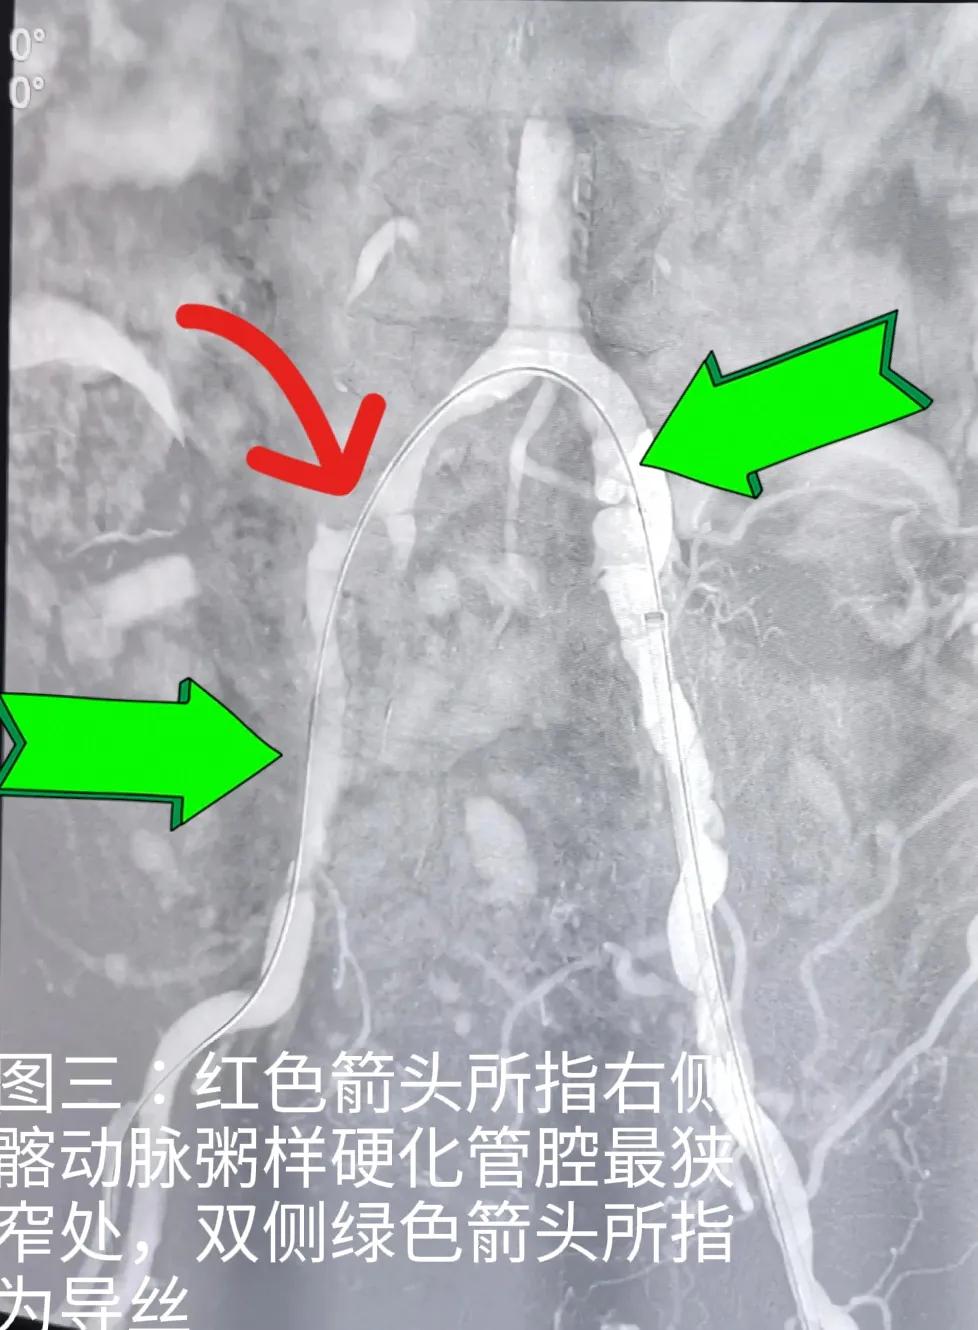

图四:红色箭头所指右髂动脉狭窄处介入医生用球囊扩张后植入支架,绿色箭头所指是导丝

图一至图五是2022年9月初浙江普陀医院(公立)骨科医生对退休教师李某某髂动脉,股动脉闭塞性动脉硬化进行介入治疗前后血管造影对比。显示血管内支架植入后血管形态非常好,患者出院后术后一个月观察,走路时下肢疼痛完全消失,间歇性跛行症状消失,两下肢功能完全恢复。